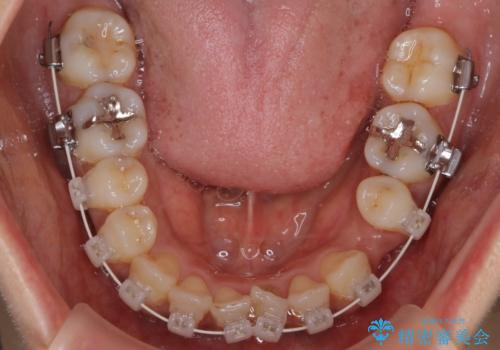

【審美装置】抜歯の本数最小限で行った矯正治療

- 審美装置

- 全体のがたつきを主訴に来院されました。4番目の歯を4本抜歯も検討しましたが、口元が下がりすぎてしまうリスクと2番目の転位うが著しく並べるのにかかる期間を考慮し、変則的な抜歯をし、並べる計画を立てました。

抜歯矯正のため2年はかかってしまいましたが、きれいに並び患者様にも満足頂きました。